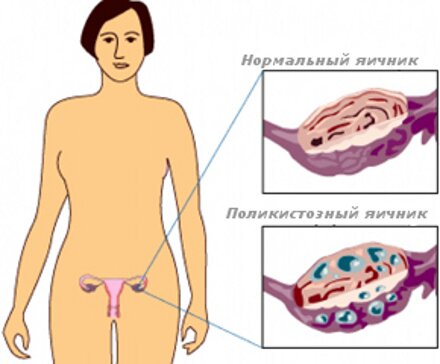

Синдромом поликистозных яичников называется эндокринное заболевание, сопровождающееся Далее...